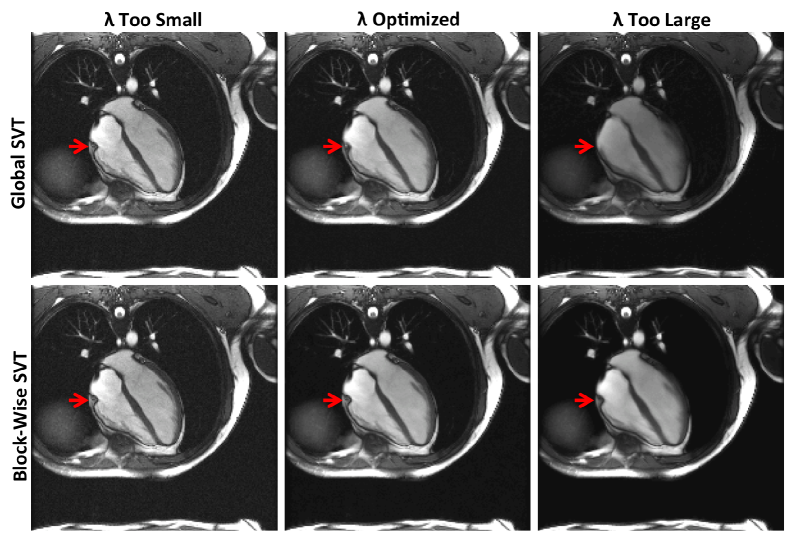

Figure 5: Global and block-wise SVT denoising results for a bSSFP long-axis cine cardiac MRI series. The effect of selecting too high or low a threshold value, as compared to the MSE/SURE optimal value is demonstrated. The red arrow identifies the tricuspid valve of the heart, which exhibit a large degree of motion through the sequence. All images are identically windowed and leveled.

Figure 5 demonstrates the effect of sub-optimally selecting the threshold value for both global and block-wise SVT. In particular, over- and under-estimates, along with the SURE-optimal values are applied within SVT. For both SVT strategies, under-estimation of λ𝜆\lambda fails to remove noise as expected. Conversely, over-estimation of λ𝜆\lambda leads to spatio-temporal blurring by both strategies albeit in different manners. In global SVT, temporal blurring occurs near areas of high motion like the tricuspid valve of the heart (indicated via the red arrow). However, less active areas like the pulmonary branching vessels, seen just above the heart, are undistorted. Some background noise also remains visible. In the block-wise SVT result, these characteristics are essentially reversed—minimal temporal blurring is induced but there is noticeable spatial blurring and loss of low-contrast static features. Noise is, however, strongly reduced. A compromise between these extremes is made by the SURE-optimized results. As suggested by Figure 6a, block-wise SVT offers stronger noise suppression (see Figures 6b-c) without inducing spatial or temporal blur, the latter which is seen even in the optimized global SVT result. This example highlights the sensitivity of SVT-denoising performance on parameter selection, and the importance of having a disciplined framework for choosing threshold values. Also of note is that, even after empirical pre-whitening, multi-channel MRI noise may not be exactly iid Gaussian. Nonetheless, SURE allows production of extremely reliable results.